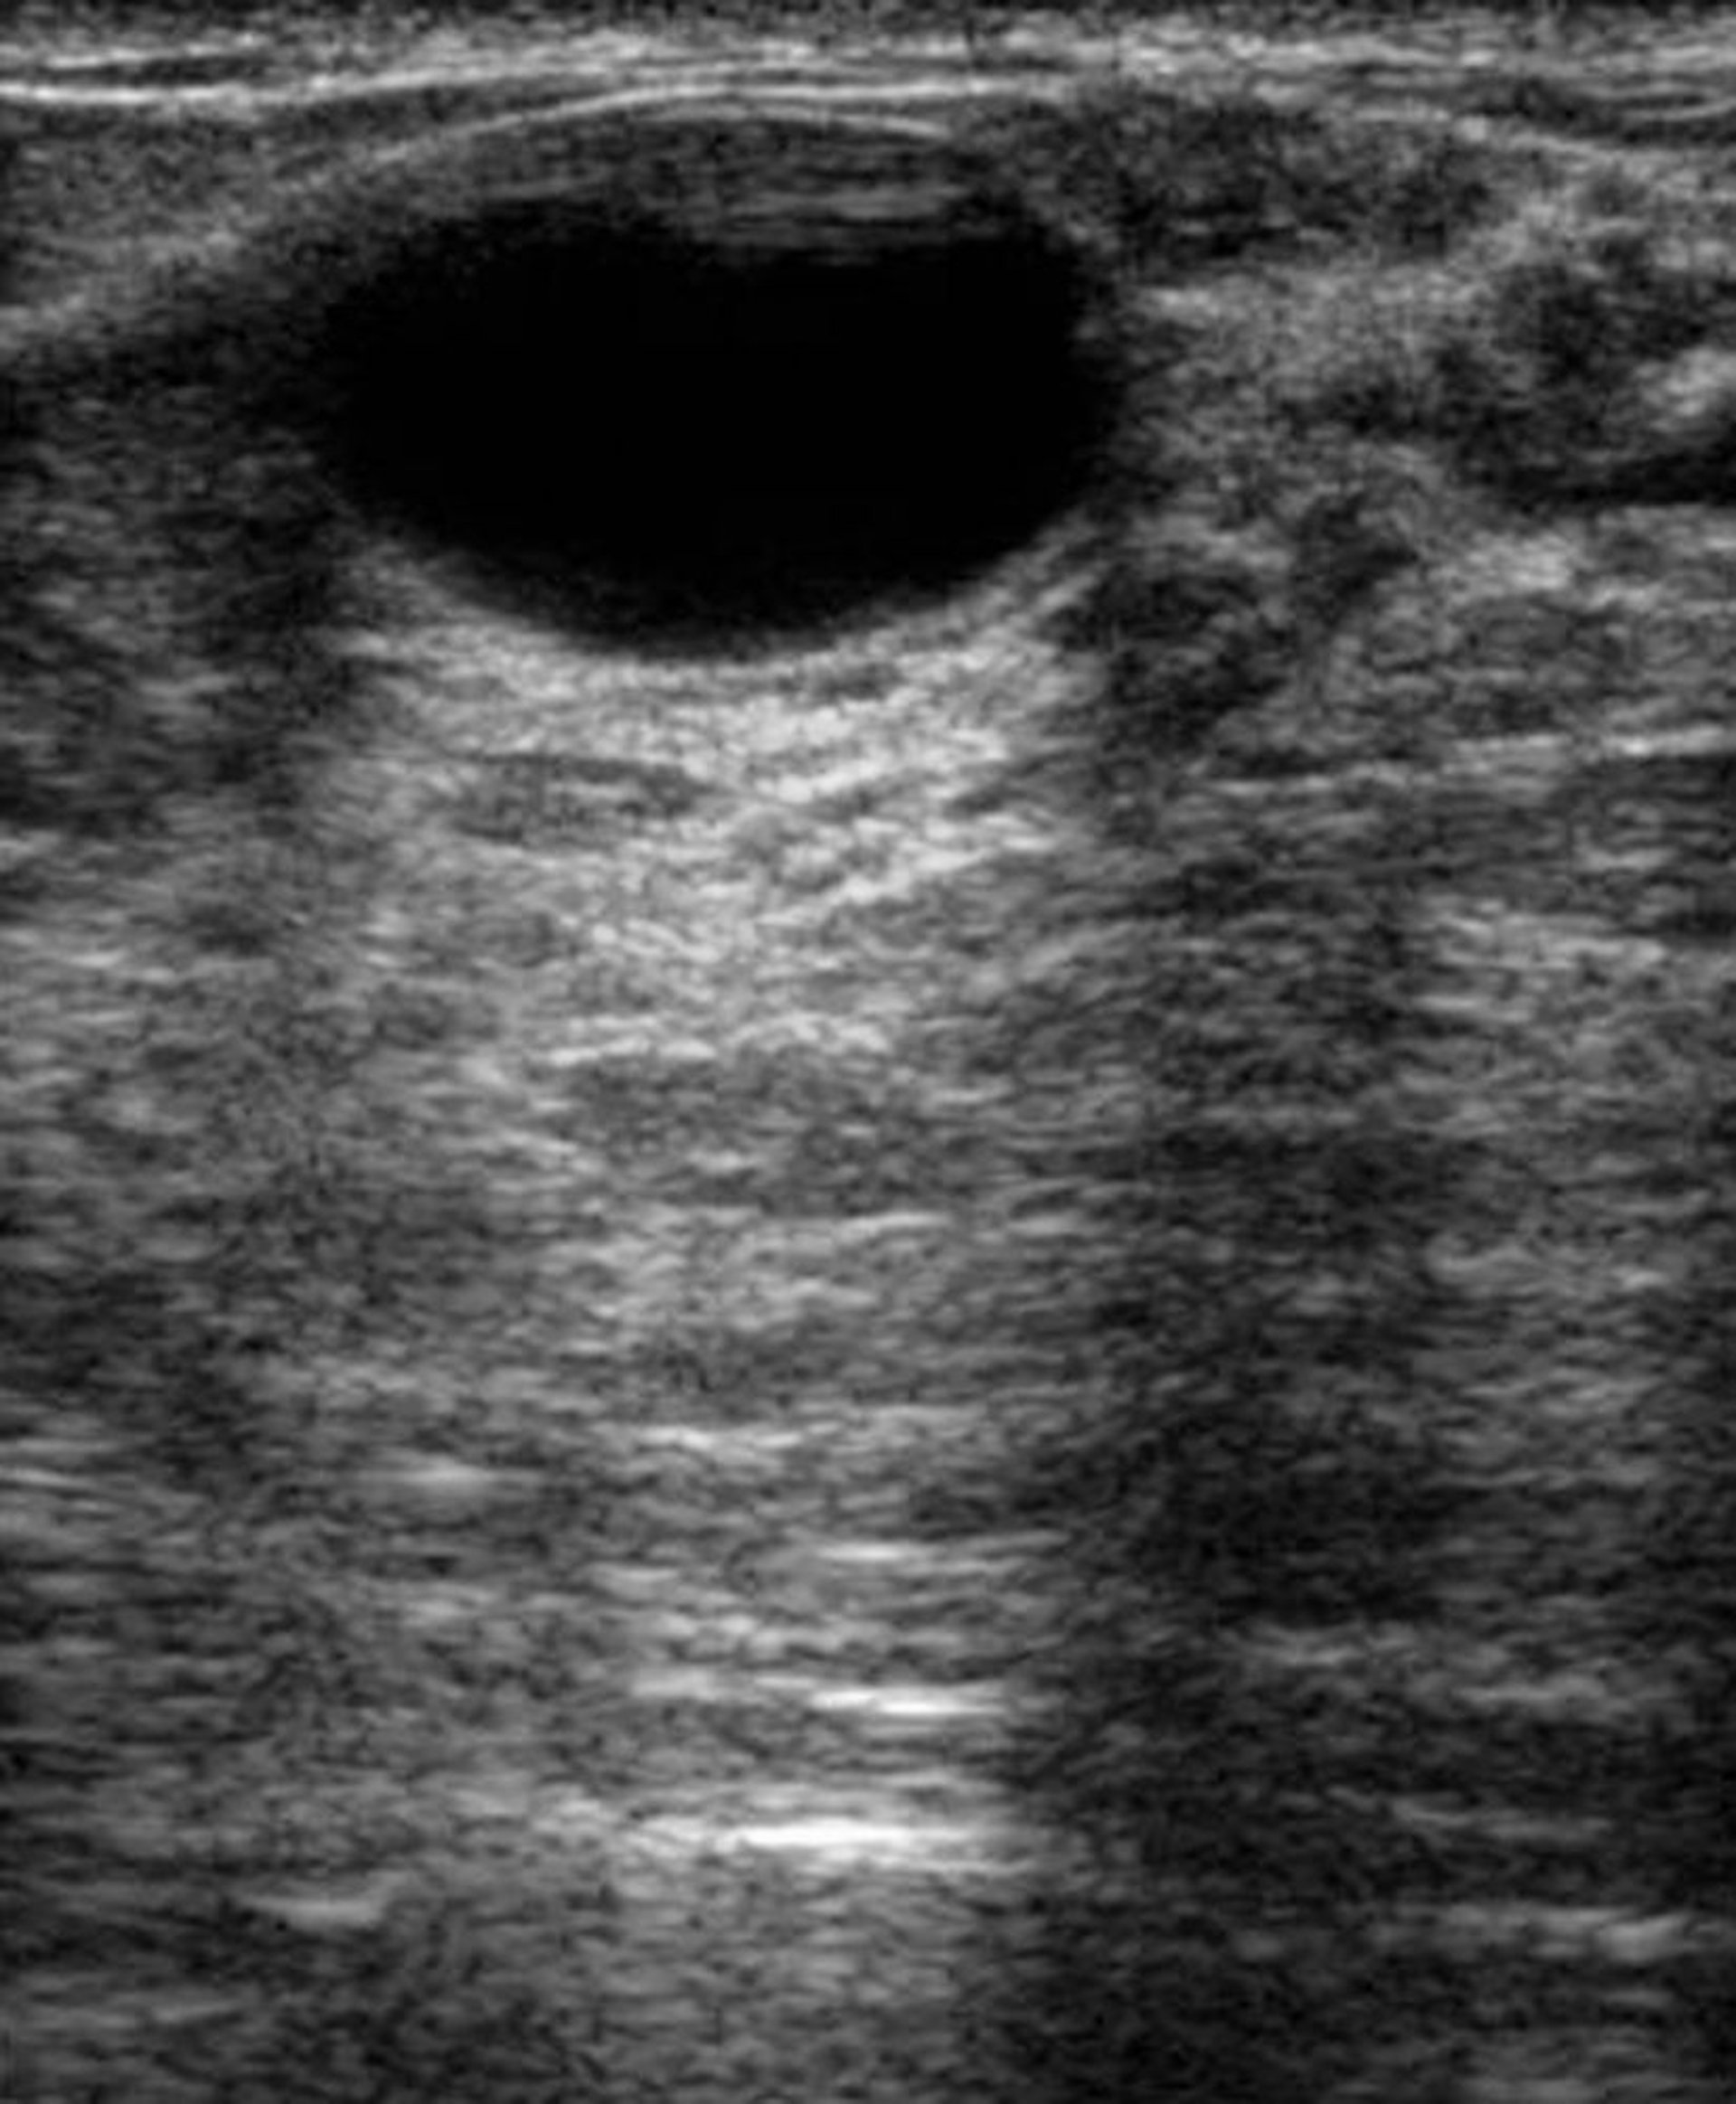

Lần siêu âm vú này của một bệnh nhân bị bệnh xơ nang cho thấy một u nang ở trung tâm phía trên. U nang là những túi chứa đầy chất lỏng thường lành tính.

BÁC SĨ NAJEEB LAYYOUS/SCIENCE PHOTO LIBRARY